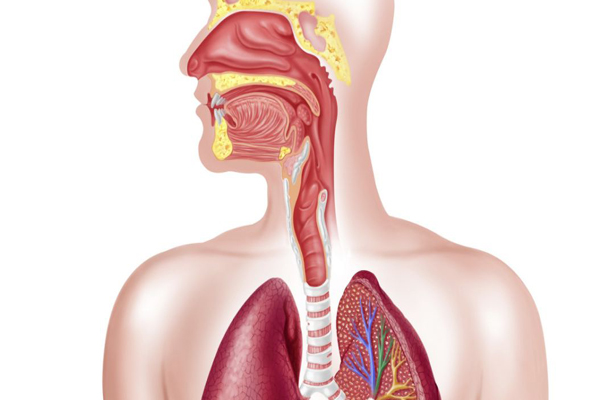

Respiratory Complaints